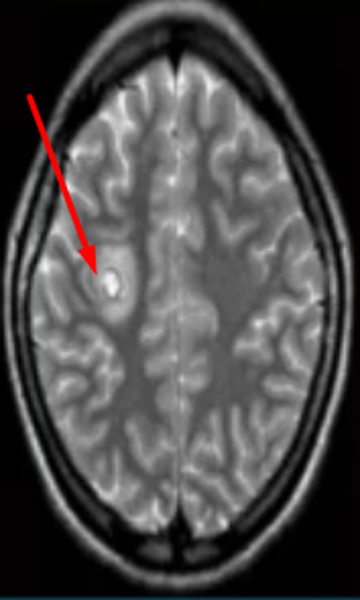

Иллюстрации и пояснения: гиподенсивный очаг на КТ головного мозга